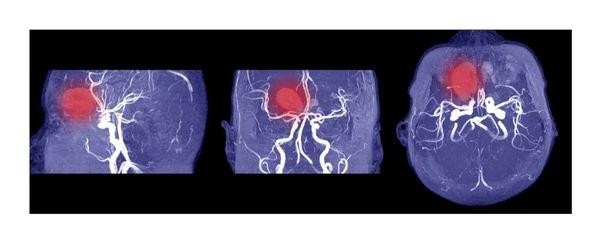

Diagnostic Imaging Techniques

Computed Tomography (CT) scans

are the first-line diagnostic tool for intracranial hemorrhage. Their speed and sensitivity to acute bleeding make them indispensable in emergencies.

CT imaging delineates the hemorrhage’s location, size, and type, and reveals mass effect or midline shift. This allows us to distinguish between subdural, epidural, intracerebral, and subarachnoid bleeds.

CT angiography

is used to identify bleeding sources, particularly when vascular abnormalities are suspected. It involves contrast dye to visualize vessels and pinpoint ruptures.

We calculate hematoma volume from imaging; clots over 30 ml often require surgical evacuation.

Midline shift greater than 5 mm is a significant indicator for surgical decompression.